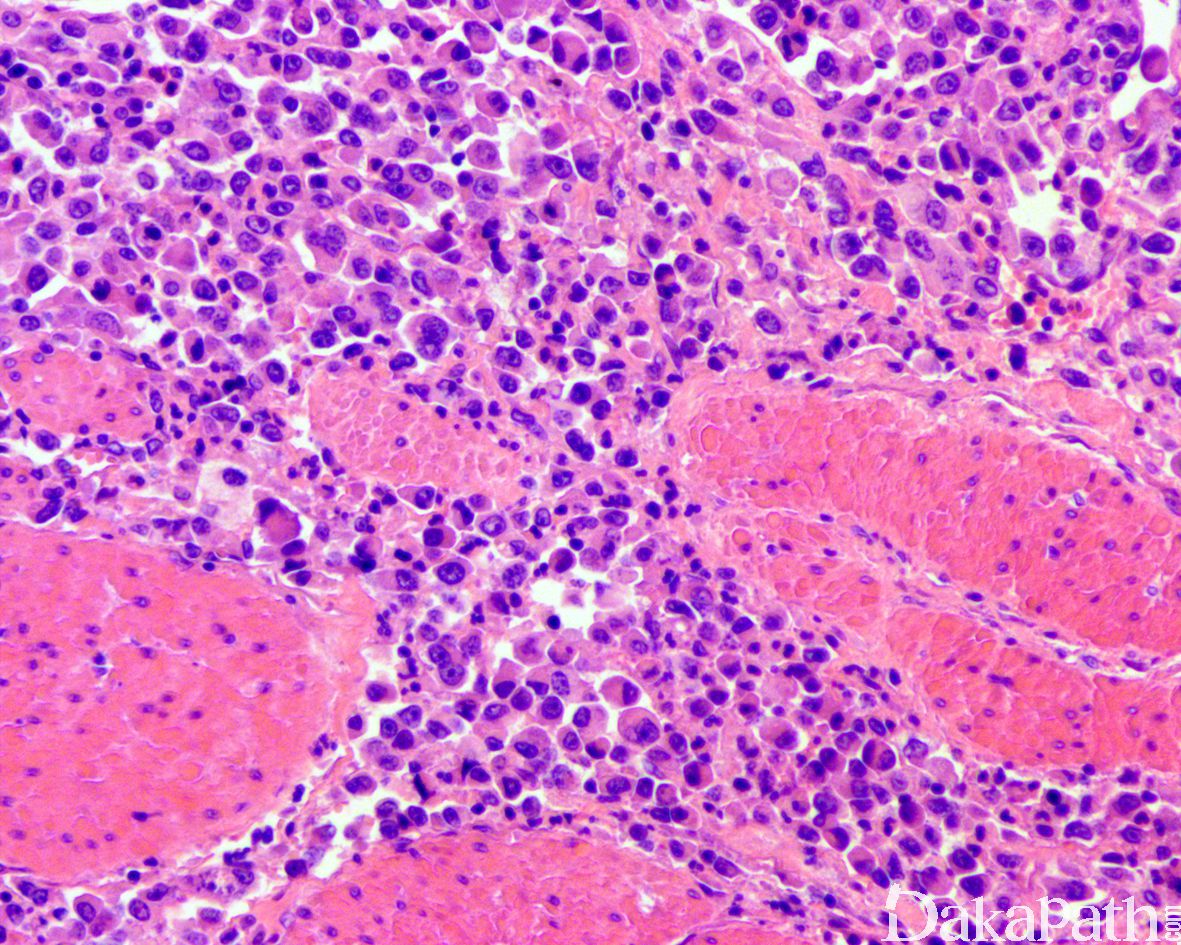

组织学表现为在疏松或黏液样间质中出现弥漫性排列的单个肿瘤细胞;

肿瘤细胞胞质透亮或嗜酸性,核大、中位或偏位,具有小核仁,似浆细胞或淋巴细胞,多形性不明显;

部分病例可见原位尿路上皮癌或乳头状尿路上皮癌,部分病例的表面黏膜可完全正常;

常见脉管内癌栓。浆细胞样尿路上皮癌可沿着筋膜播散并浸润至腹膜,因此应对肿瘤进行广泛的取材。